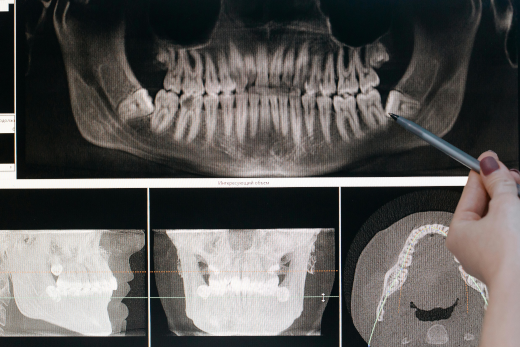

• panoramique dentaire

Radiologie

Panoramique dentaire numérique

Imagerie complète pour l’évaluation de la santé bucco-dentaire.